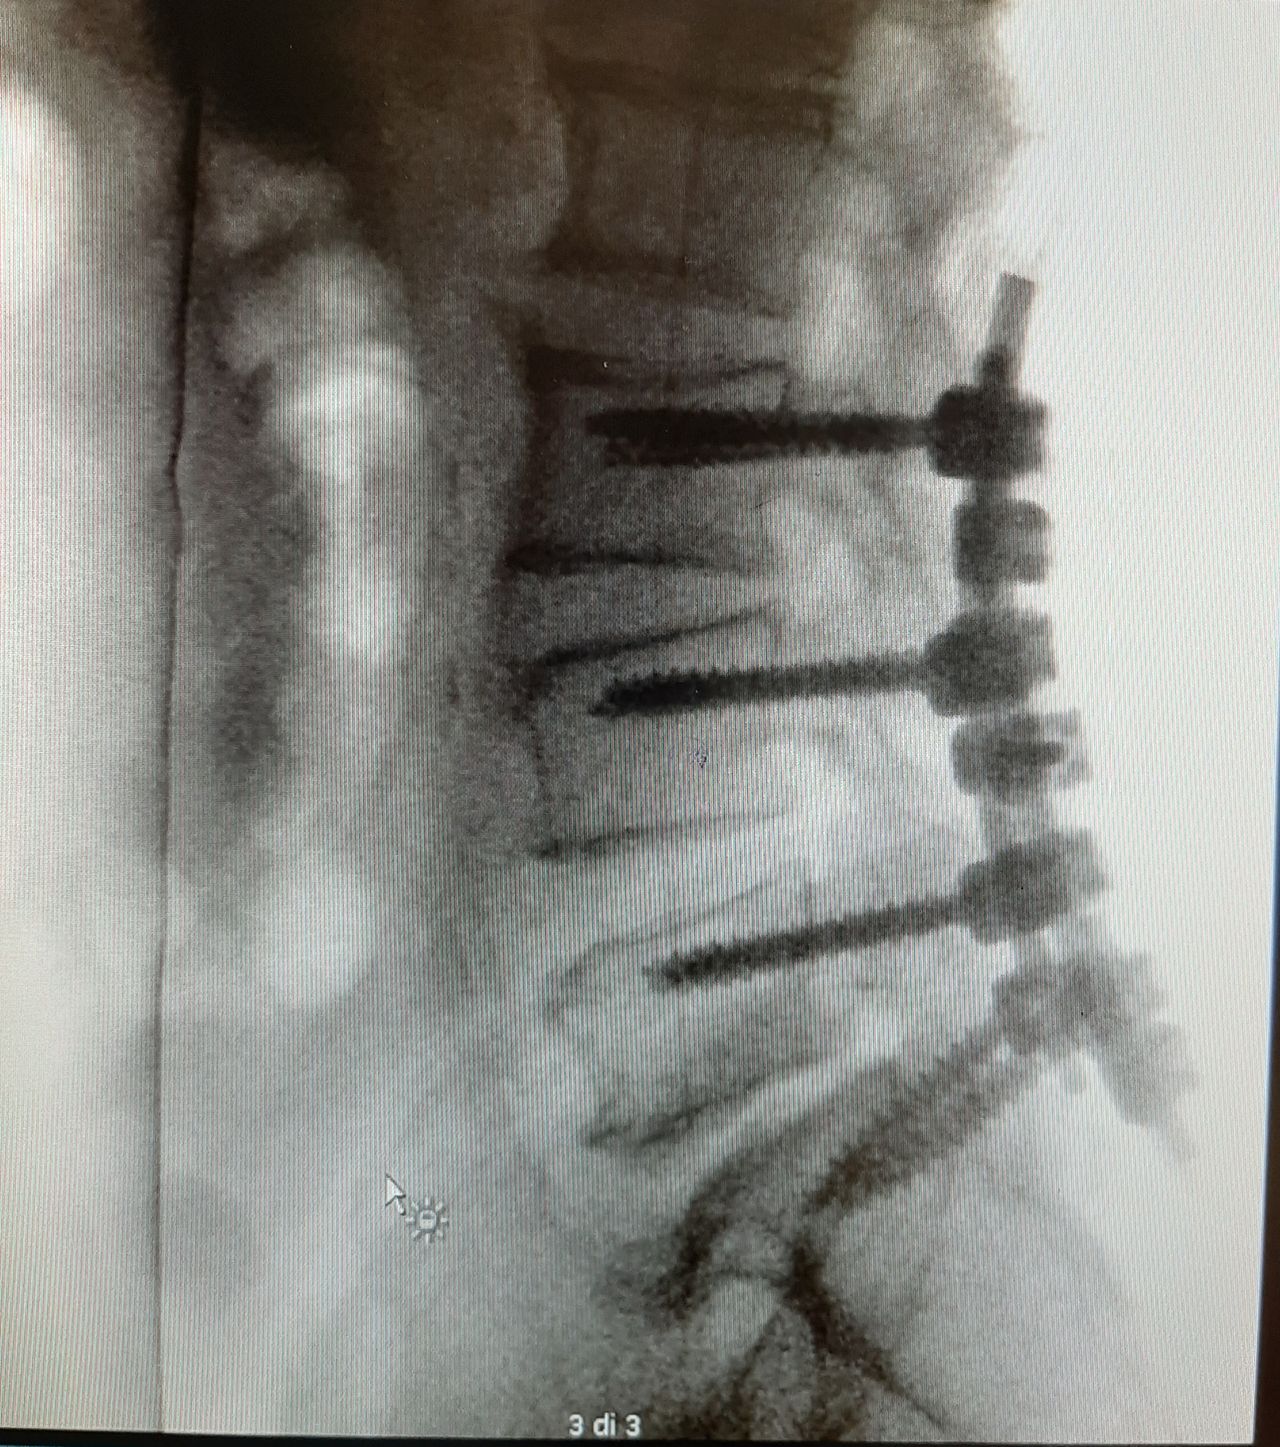

Laureata in Medicina e Chirurgia summa cum laude presso l’Università degli Studi di Palermo nel 1996. Specializzata in Neurochirurgia summa cum laude presso l’Università di Messina. Fellow di Neurochirurgia pediatrica. Da febbraio 1999 a Settembre 2000 frequenza del reparto e della sala operatoria di Neurochirurgia Pediatrica dell’ Hospital Infantil de Mexico Federico Gomez a Città del Messico. Dal 07/12/2010 Dirigente medico con contratto a tempo indeterminato presso l’Unità Operativa di Neurochirurgia di Ospedali Riuniti Villa Sofia-Cervello di Palermo. Precedentemente ha svolto la propria attività di neurochirurgo presso il Policlinico Morgagni di Catania, Villa Maria Pia Hospital di Torino, e presso la Casa di Cura Pasqualino-Noto di Palermo in regime libero- professionale. Ha acquisito competenze tecniche in chirurgia spinale mini-invasiva e open della colonna vertebrale sia in patologia degenerativa che in oncologica e nella patologia cranica post-traumatica ed emorragica. E’ coautore di diverse pubblicazioni scientifiche in riviste indexate. Ha insegnato Neurochirurgia al corso di formazione specifica in medicina generale (CEFPAS).

• Spondilolistesi

• Lesione spinale

• Fratture vertebrali

• Stenosi del canale